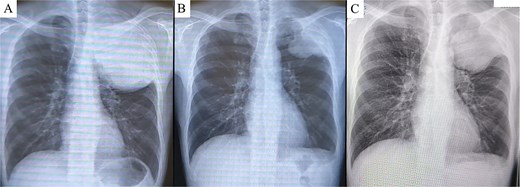

Chest X-ray prior to treatment revealed a large mass extending from the left lung apex to the upper lung field (A), which markedly decreased in size following immunotherapy (B). However, during the 4-week interval between the end of immunotherapy and surgery, the tumor demonstrated regrowth (C).